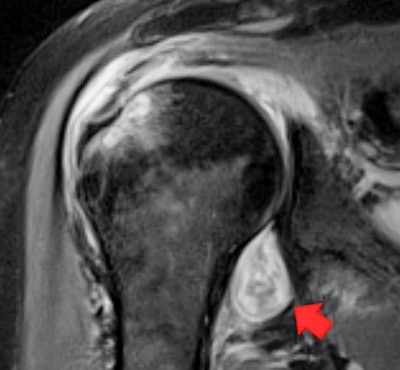

"If a patient has persistent shoulder pain that started after contracting COVID, their primary care provider might order an MRI/ultrasound," he said. "If a radiologist knows COVID can trigger inflammatory arthritis and imaging shows joint inflammation, then they can send a patient to a rheumatologist for evaluation."